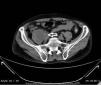

Common and applicable diagnostic methods are available for brucellosis. However, its life-threatening complications remain critical. Herein we present a 68-year-old patient who complained of leg pain for two months. At admission he had absent pulse in the left femoral and bilateral popliteal arteries. Laboratory test results were leucocytes 8700/mm3, CRP 86mg/L, and ESR 47mm/h. Abdominal CT revealed images consistent with mural thrombus in the suprarenal segment of abdominal aorta, total occlusion and hypodense thrombus material completely filling the aortic lumen through infrarenal segment extending to lumens of the caudal, bilateral common and superior iliac arteries (Figs. 1–3). No paleness, coldness or color change was detected in the lower extremities. The patient had fever, right inguinal swelling, and sweating. Abdominal CT showed an aortic thrombus and a hypodense lesion of 58mm×61mm×100mm in the right psoas muscle. The repeated Brucella STA test was positive in 1:5120 titer. USG-guided drainage of the psoas abscess was performed and a treatment with doxycycline and rifampicin was administered for three months (Fig. 4). The patient was not operated on and progressed with no clinical complaints.